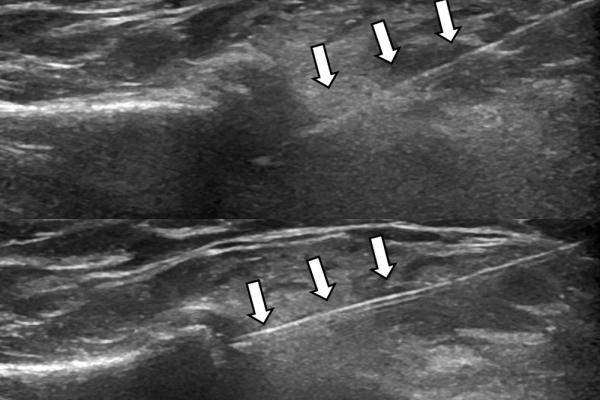

Υπό συνεχή υπερηχογραφική παρακολούθηση είναι δυνατόν να πραγματοποιηθούν κατευθυνόμενες εγχύσεις σε ορθοπαιδικές και ρευματολογικές παθήσεις. Αρχικά εντοπίζεται η παθολογική περιοχή και στη συνέχεια εξετάζεται η βέλτιστη οδός προσπέλασης. Ακολούθως γίνεται υπό άμεση και συνεχή υπερηχογραφική παρακολούθηση οι απαραίτητοι χειρισμοί και έγχυση φαρμάκων ακριβώς στη θέση της βλάβης.

Εχει αποδειχθεί ότι με την υπερηχογραφική καθοδήγηση εξασφαλίζεται:

- μεγαλύτερη ακρίβεια και αποτελεσματικότητα (αφού η έγχυση/θεραπεία γίνεται ακριβώς στηνπαθολογική περιοχή)

- καλύτερη ανοχή από τον ασθενή (λιγότεροι τραυματικοί χειρισμοί αφού έχουμε άμεση και συνεχή εποπτεία της βελόνας)

- μεγαλύτερη ασφάλεια (αποφυγή τρώσης νεύρων, αγγείων, γειτονικών ανατομικών δομών).